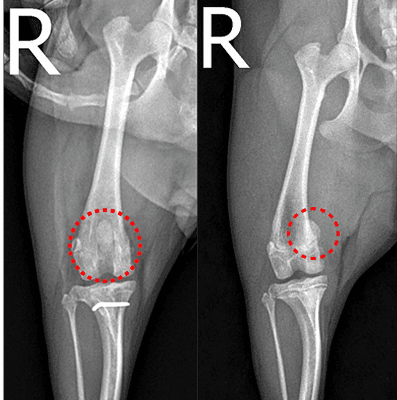

무릎뼈가 정상 위치에서 벗어나며 절뚝거림, 다리 들기, 통증이 반복될 수 있습니다. 단계와 다리 정렬 상태에 따라 수술 방법이 달라집니다.